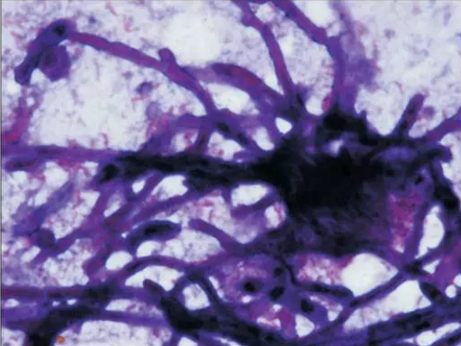

初步診斷為口腔毛霉菌病。取部分軟腭組織做病理學檢查。病理檢查顯示組織中含有大量無包膜的真菌、壞死血管組織,結果支持毛霉菌病的診斷。